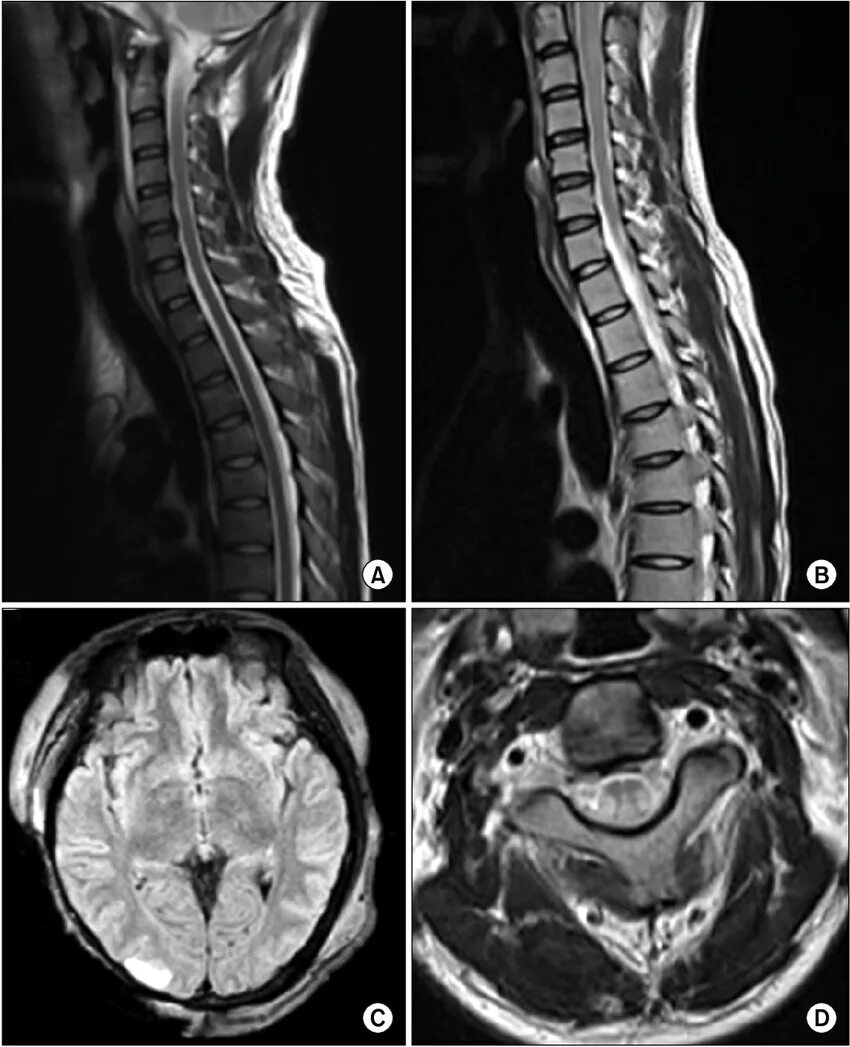

Spine mri